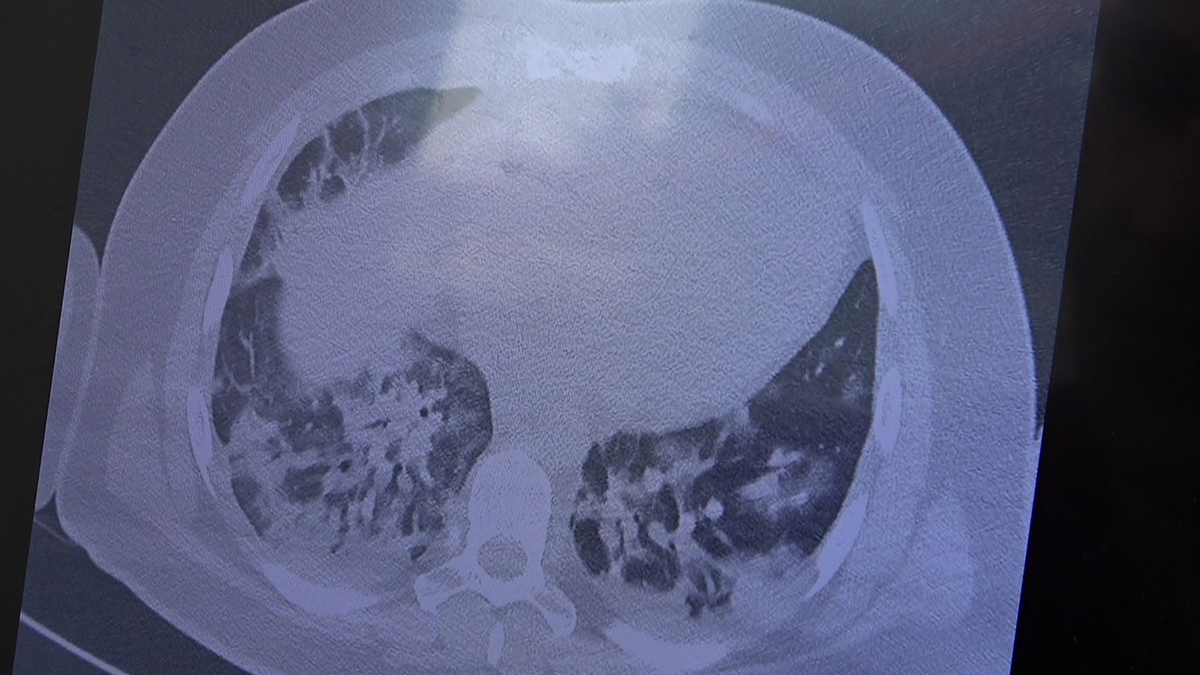

'CİDDİ AKCİĞER TUTULUMLARI'

Gençlerin akciğer tomografilerini inceleyen Özkaya, "İki vaka örneği hakkında bilgi vermek istiyorum. İnsanlara bu işin bitmediğini anlatmamız lazım. 30 yaşında aşı olmamış bir hastamızın filminde çok yaygın akciğer hasarı var. Şu an kendisi yoğun bakımda tedavi alıyor. Öte yandan 25 yaşında bir hastamız var. İki doz Kovid aşısını da olmamış. Ciddi akciğer tutulumları var. Çok ciddi solunum sıkıntısı ile Kovid servisinde yatıyor. Şu an hasta profilimizin büyük bir kısmını bu durum oluşturuyor” ifadelerini kullandı.